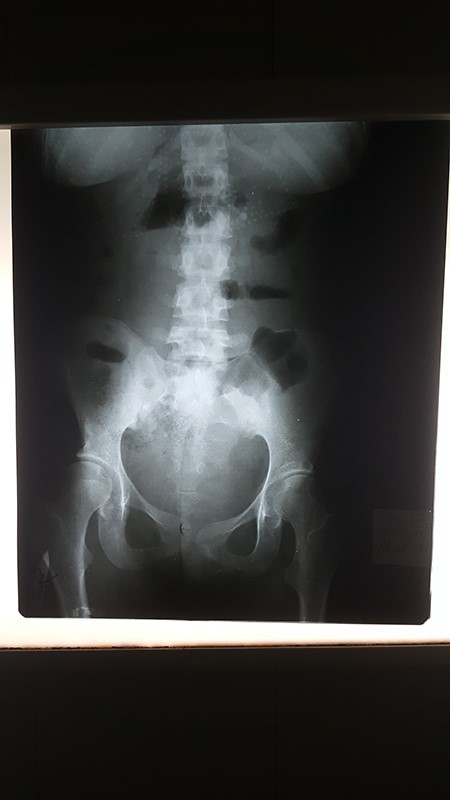

Physical examination revealed mild abdominal distension, mild tenderness in the periumbilical region, tympanites in the left side of the abdomen and no loss of weight. Abdominal ultrasonography showed a mild amount of serous fluid in the abdomen and pelvis, the abdominal X-ray (AXR) showed air-fluid levels within the transverse colon and absence of gases in the pelvis (Fig. 1), chest X-ray and laboratory tests were normal.

AXR shows air-fluid levels within the transverse colon and absence of gases in the pelvis.